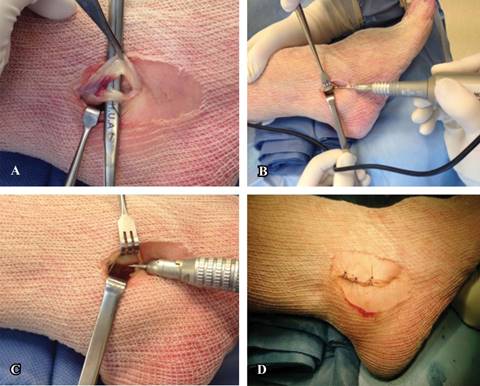

El abordaje miniinvasivo consta de 3 cm posterolateral en palo de hockey (Figura 2). Se realiza una disección roma hasta el plano óseo, creando un colgajo de piel completa para evitar la necrosis cutánea; se incide la vaina peronea distal al peroné. Si el retináculo superior está intacto (algo poco frecuente), se incide sobre el hueso y se eleva desprendiéndolo del peroné, dejando un manguito de tejido en el peroné distal; así, se retraen los bordes del retináculo para facilitar una reparación posterior. Se escinde la membrana sinovial inflamada y se inspeccionan los tendones peroneos, que se desbridan y/o reparan con suturas no reabsorbibles (Figura 2).

Figura 2: A) Lesión del tendón peroneo corto. B) Sistema de fresas MIS. C) Dirección de la fresa hacia la cortical posterior evitando inserción del calcáneo peroneo. D) Síntesis del abordaje posterolateral miniinvasivo.

En el caso de presentar haces musculares bajos y/o un peroneo cuarto, se procede a la remoción de los mismos. Se expone la punta del peroné, evitando la lesión del ligamento calcáneo-peroneo y se introduce una fresa Shannon 44 larga, de distal a proximal dentro del peroné en paralelo a la cortical posterior, adelgazando la misma mediante un fresado secuencial y se progresa con una fresa quirúrgica Wedge Burrs de 4.1 (Figura 2). Una vez que la cortical posterior se ha adelgazado (fresado de esponjosa subcortical) lo suficiente, se impacta dicha cortical, generando una profundización cóncava del surco y preservando, de este modo, la superficie de deslizamiento fisiológica de los tendones.

Todo el tendón peroneo corto y al menos 50% del peroneo largo deben quedar cubiertos por el borde del peroné luego del procedimiento, cuando están en reposo. Los autores recomiendan realizar maniobras de flexión dorsal y eversión del tobillo, bajo visualización directa para confirmar la no luxación de los tendones. Se escinde el tejido redundante del retináculo peroneo superior y se hace avanzar el retináculo residual hacia el lecho cortical mediante anclaje de sutura de 5 mm en esponjosa. Se realiza el cierre de la piel con Nylon 4.0.